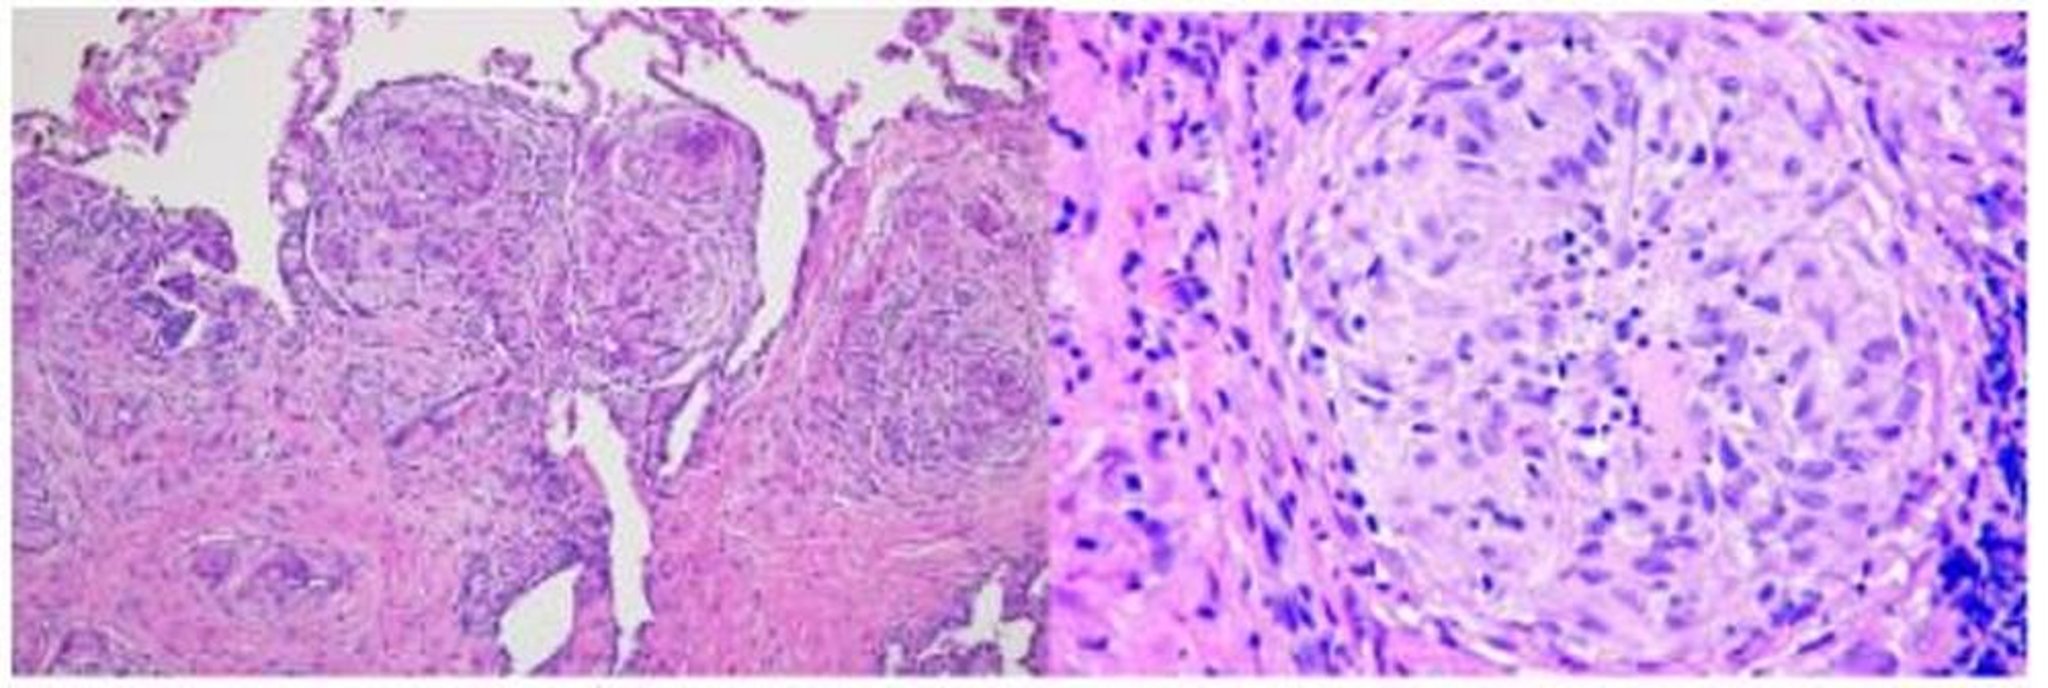

Sarcoidose (histopatologia)

Nessa imagem, uma biópsia pulmonar de um paciente com sarcoidose mostra granulomas ao longo do feixe broncovascular (coloração com hematoxilina e eosina, baixa ampliação; à esquerda) e granuloma sarcoide com células multinucleadas muito grandes no centro dos granulomas (alta ampliação; à direita).

Imagem cedida por cortesia de Birendra P. Sah, MD, FCCP.